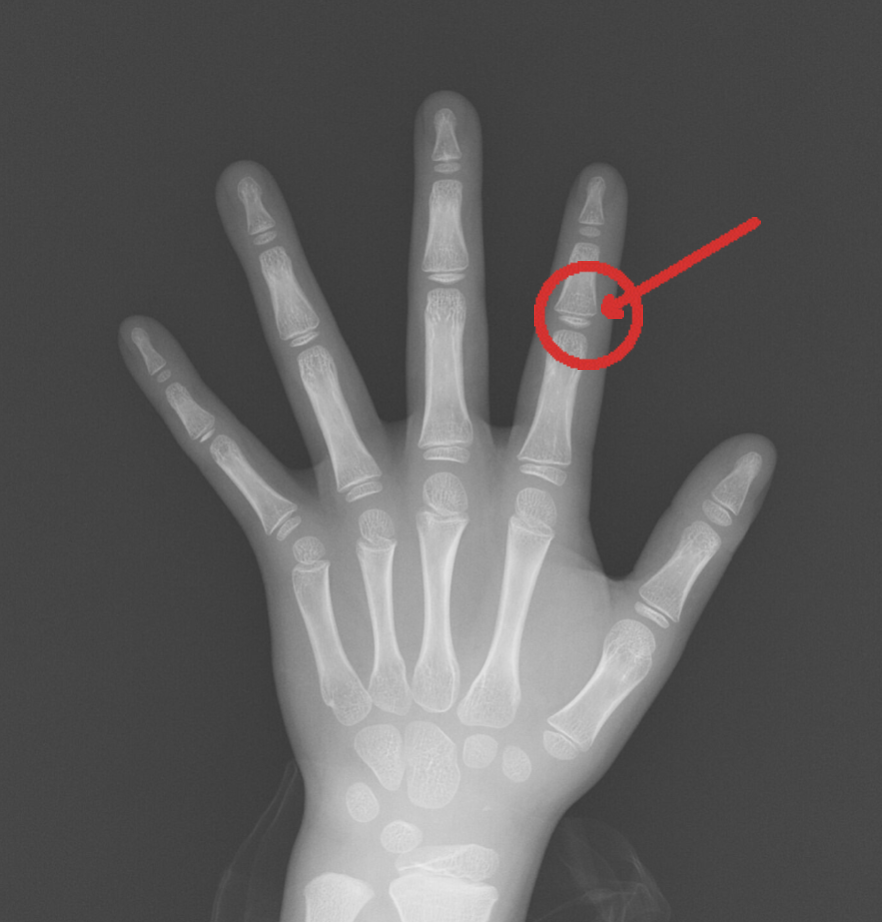

骨年齢の検査

- 手のレントゲンで骨の成熟度をチェック

- 実際の年齢に対して骨の成長が遅れているかを確認

- 治療でどのくらい身長を伸ばせる可能性があるかの目安になる

※F君(8歳・男の子)骨端線(赤矢印部分)が見えます